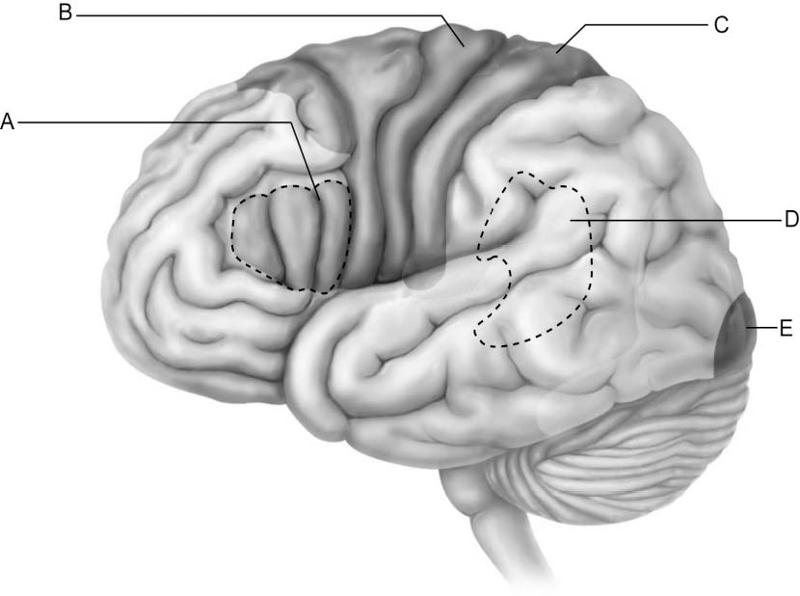

Which letter indicates the primary visual cortex, which receives

information from neurons in

the retina of the eye?

A)

A

B) B

C) C

D) D

E) E

E

Which letter indicates Broca's area, which controls the motor

movements necessary for

speaking?

A) A

B) B

C)

C

D) D

E) E

A

Which letter indicates Wernicke's area, which is important for

understanding spoken words?

A) A

B) B

C) C

D)

D

E) E

D

Which letter indicates an area that is characterized by huge neurons

known as pyramidal cells?

A) A

B) B

C) C

D)

D

E) E

B

Which letter indicates the primary somatosensory cortex?

A)

A

B) B

C) C

D) D

E) E

C